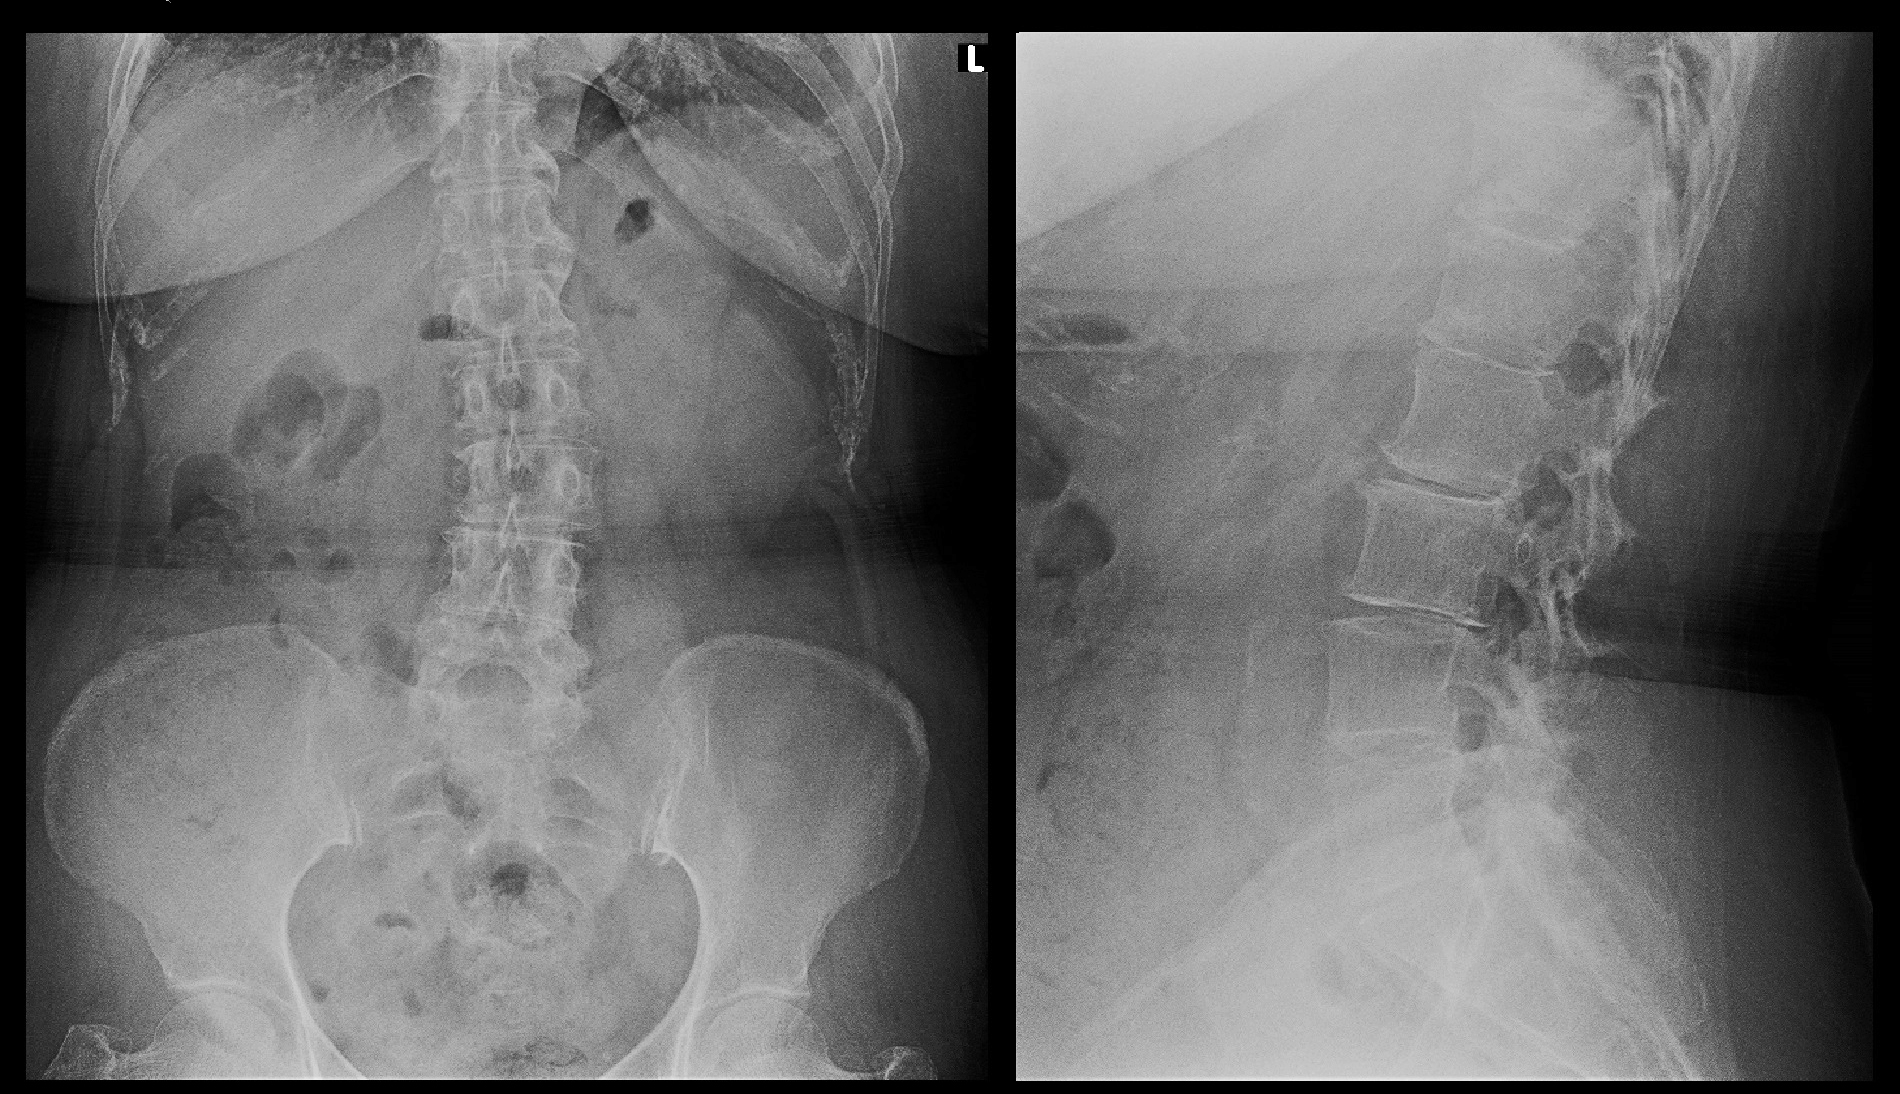

70才女 就眠時Xp.jpg右臀部痛ですが、腰椎のレントゲン像で確認できる限り右股関節には異常を認めません。年相応の老化現象の所見が見られる腰椎レントゲン像です。